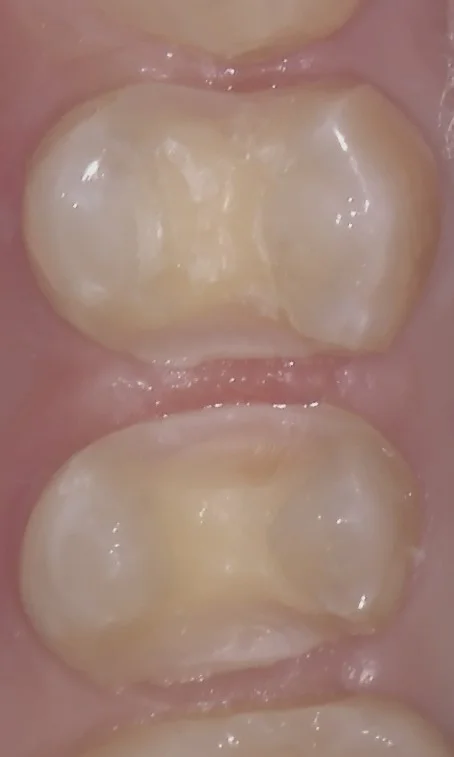

そして詰め終わったのがこちらです。

いつもの私のデザインと歯少し違いますが、反対側の歯と同じデザインを意識しました。

良い感じに再現できたと思います。